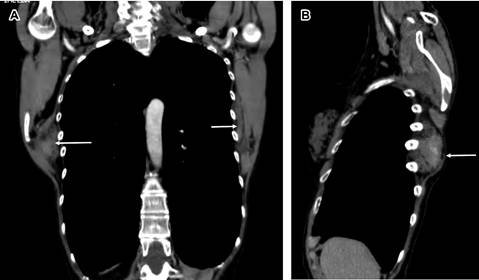

Figura 2: Imágenes de tomografía computarizada en cortes coronal (A) y sagital (B), se observa masa tumoral periescapular derecha con dimensiones de 7 × 5 cm que desplaza escápula hacia afuera y arriba, además de masa tumoral periescapular más pequeña en escápula izquierda.